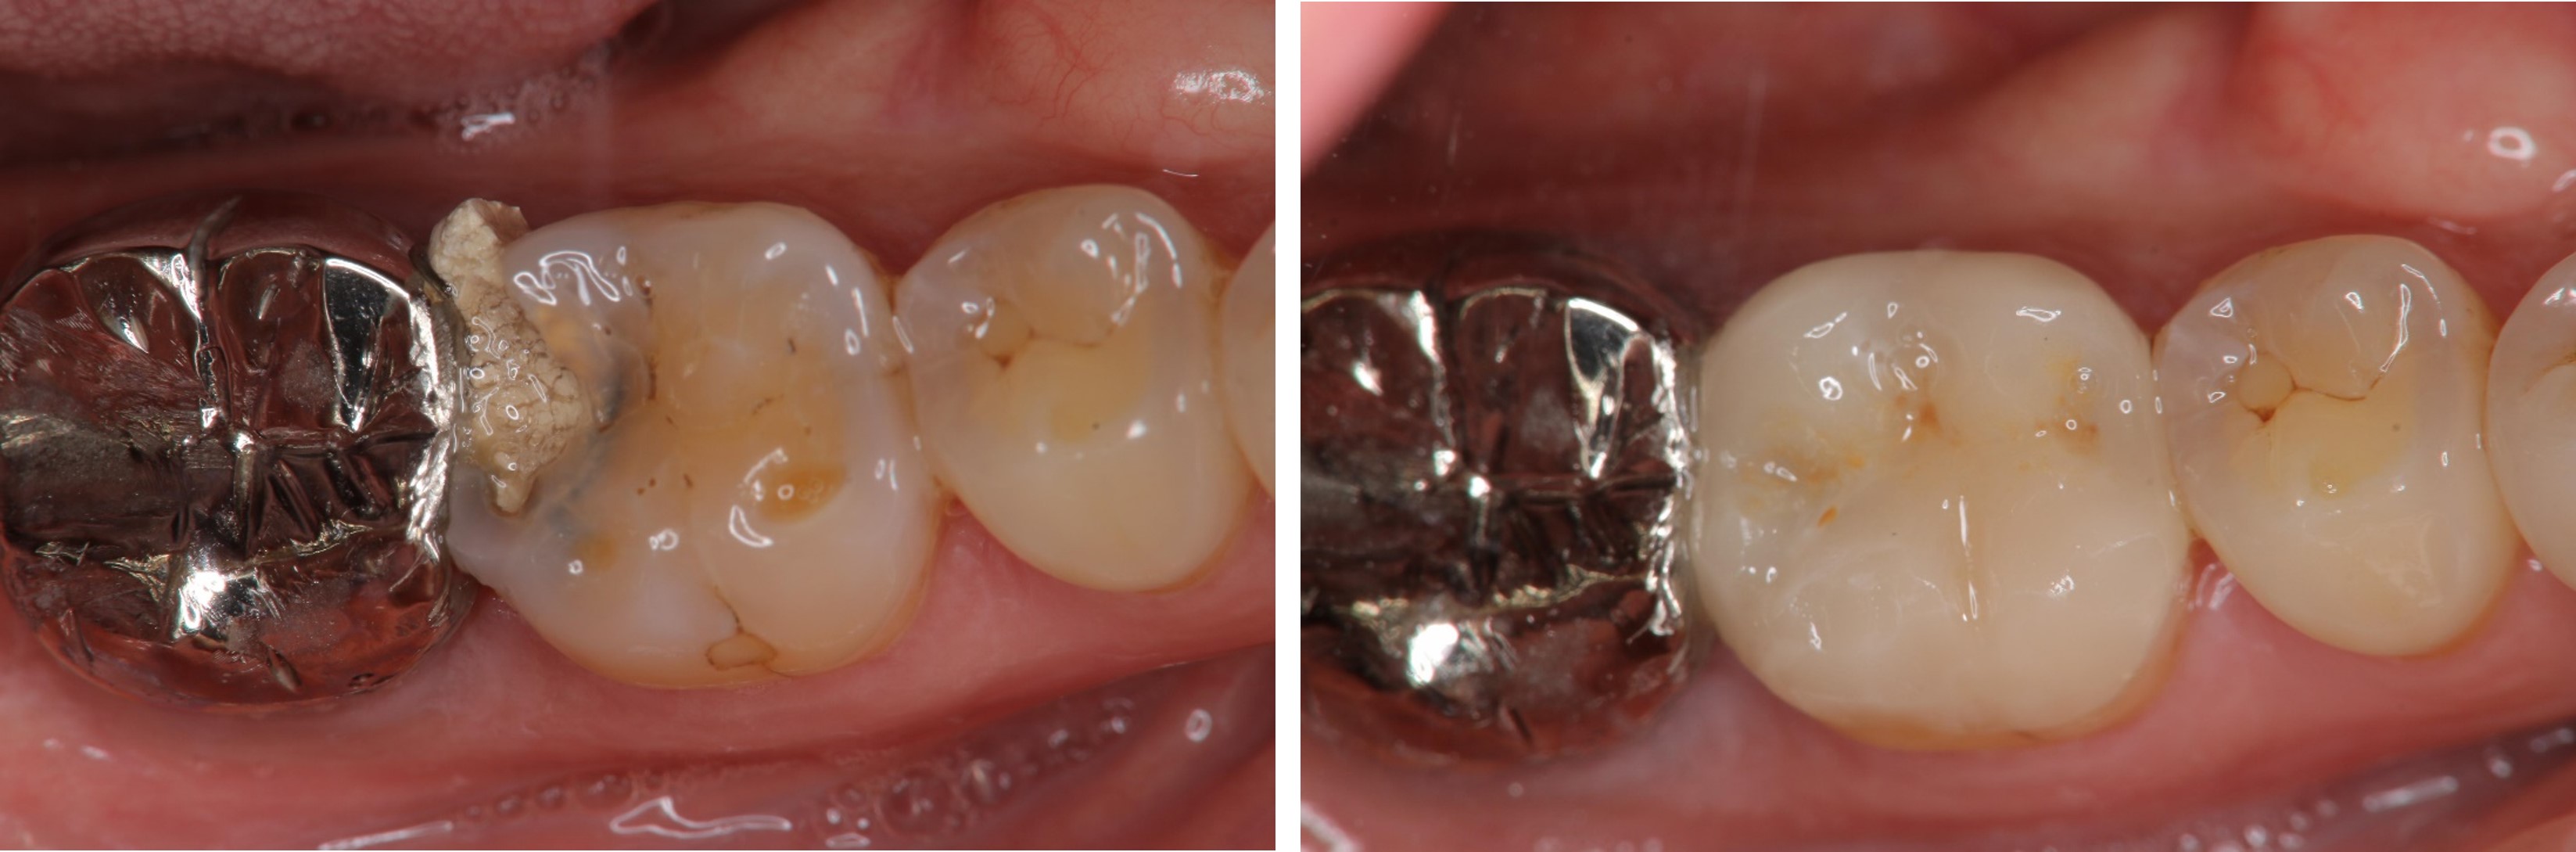

術前、術後比較

治療前,嚴重蛀牙,咬頭受損

陶瓷冠塊體是根據蛀牙的窩洞量身訂做,不管是顏色、精密度都是最佳的選擇,因此是非常美觀與持久的填補窩洞材料與技術